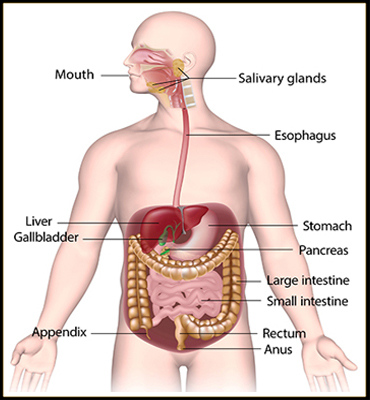

Digestive System

Digestive Problems :

- Hyperacidity

- Gas trouble

- Indigestion

- Dysentry

- Diarrhoea

- Intestinal Inflammation

- Peptic - Intestinal Ulcer

- GERD

- Colitis

- Intestinal Worms

- Liver Enlargement

- Liver Cirrhosis

- Fatty Liver